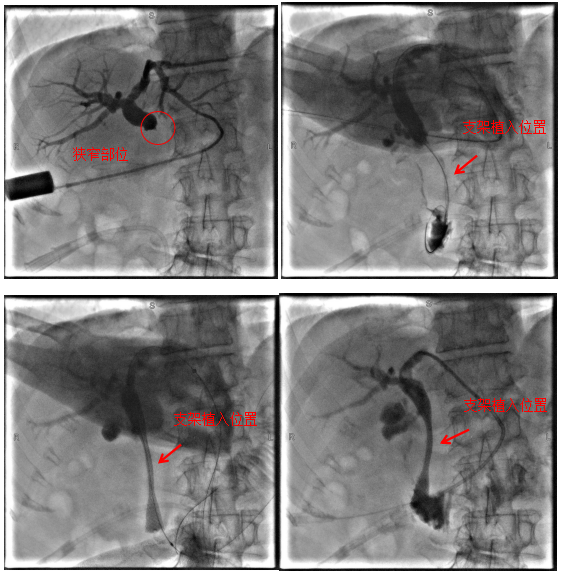

病例1

69岁老年患者,因“中上腹疼痛1周”于我院肝胆胰外科住院治疗,完善相关检查后考虑诊断为:胰腺恶性肿瘤、梗阻性黄疸等,因肿瘤分期晚并出现远处转移,已无根治性手术指征,且因肿瘤侵犯十二指肠导致肠腔狭窄,无法实施ERCP+胆道支架植入术解除胆道梗阻,经过科室团队充分评估,决定为患者行经皮经肝胆道支架植入术,手术顺利,术后患者黄疸逐渐消退,为后续治疗提供了坚实的保障。

术中影像